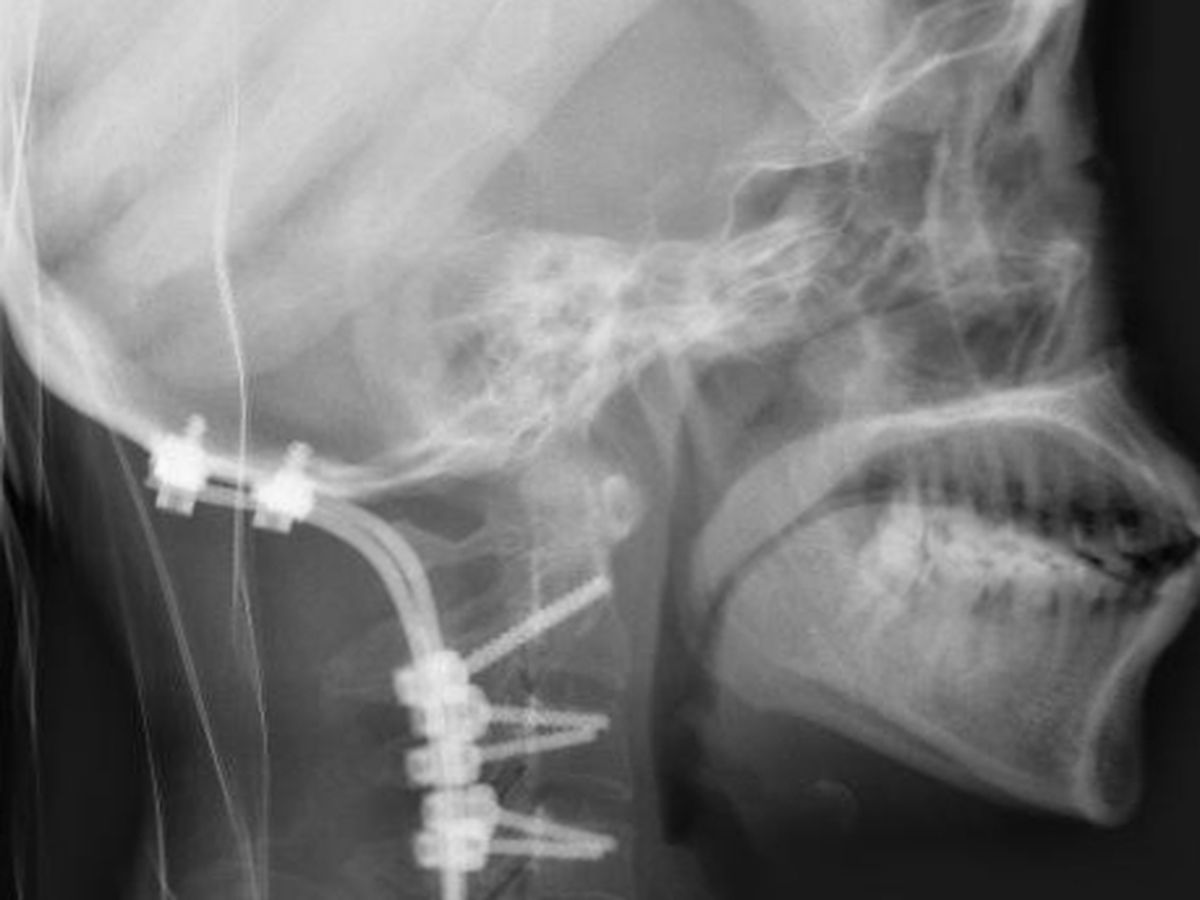

I did the tests as it was suggested and spoke to specialists, I was eventually diagnosed with Cranial cervical instability and Atlantoaxial instability, as well as a Chiari Malformation - my skull was crushing my brain stem and my nerves/vessels- and it had been happening for TEN YEARS, just getting worse and worse.

Where my symptoms were not always the same, I spent my whole life thinking it was normal to be in pain, my vision has been permanently damaged and I was having trouble walking more than a couple of feet, or eating/keeling down food, I was crawling from place to place as I felt so ill. I lost a lot of feeling in my limbs to the point of occasional paralysis and had the traditional bobblehead feeling.